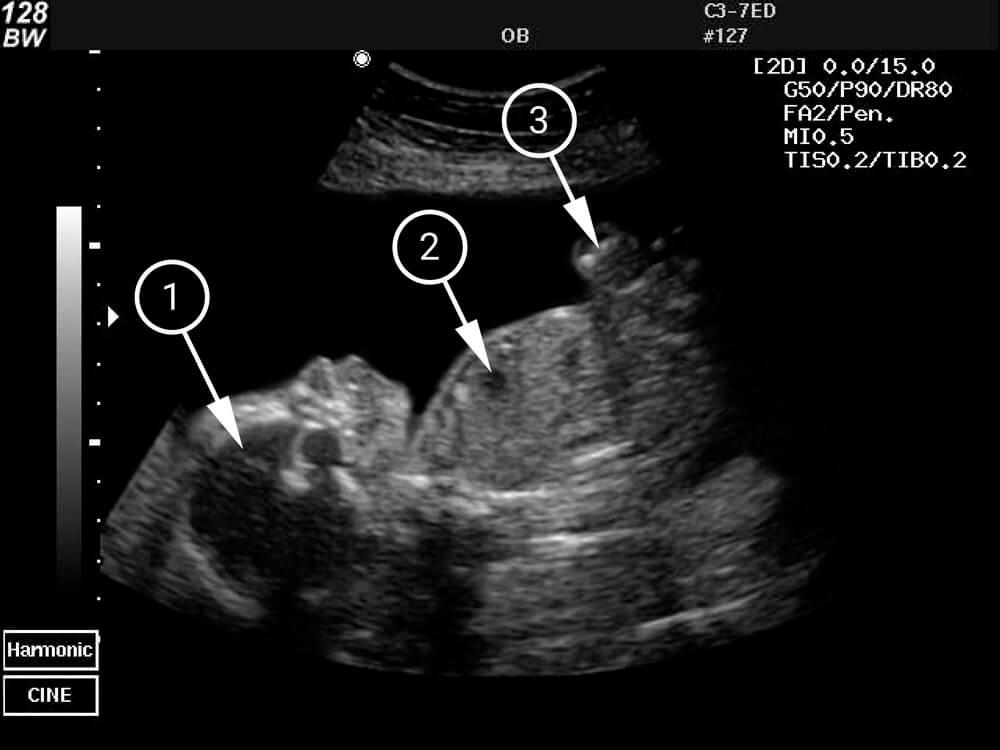

¿Qué se puede ver en la ecografía/ultrasonido?

Aquí puedes ver el perfil del bebé. Está descansando con la parte posterior de la cabeza y el pie contra las paredes del útero. En el lado izquierdo de la foto, puedes ver sus ojos, nariz, labios y barbilla. La zona oscura del pecho es su corazón.